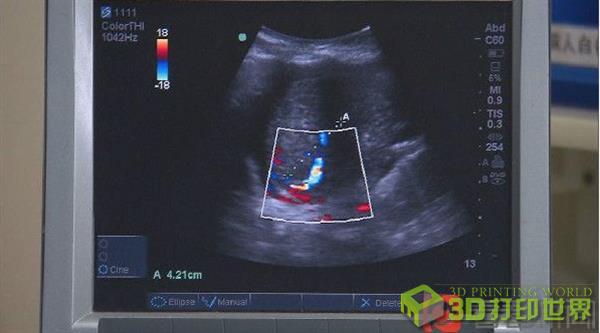

前天,志豪进行了最新一次肝脏B超检查,检查发现移植入志豪体内的肝脏体积明显增大,门静脉和肝动脉的血供也良好,肝功能正常,基本符合术前预期。